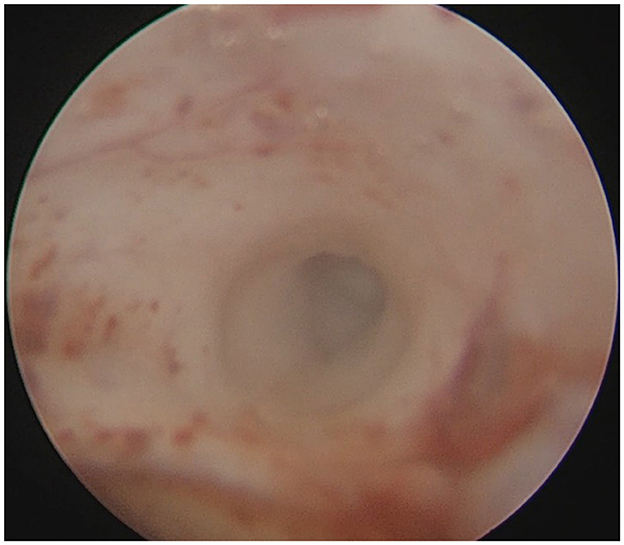

A 22-year-old male presented with intermittent dizziness and headache lasting for 2 weeks. MRI at admission revealed a cystic mass in the pineal region, accompanied by supratentorial hydrocephalus (Figures 3–5). No surgical contraindications were identified. After discussion with the patient's family, neuroendoscopic resection was performed via the Transfrontal-Transventricular-Transforaminal Approach. Intraoperatively, a 20 × 20 mm soft, well-vascularized tumor was found obstructing the cerebral aqueduct. The lesion had well-defined margins and was carefully dissected from surrounding adhesions, preserving adjacent veins and brain tissue. Macroscopic total resection was achieved en bloc (Figures 6–8). Postoperative day 1 MRI confirmed complete tumor removal and resolution of hydrocephalus (Figures 9–11). Postoperatively, no complications were observed. However, due to personal reasons, the patient was discharged on postoperative day 11. Histopathology confirmed a mixed germinoma. No recurrence or surgery-related complications were noted during follow-up.

Figure 6

Intraoperative endoscopic view showing a ~20 × 20 mm tumor obstructing the cerebral aqueduct in the pineal region.

Figure 7

En bloc macroscopic resection of the tumor.

Figure 8

Endoscopic visualization confirming patency of the cerebral aqueduct.